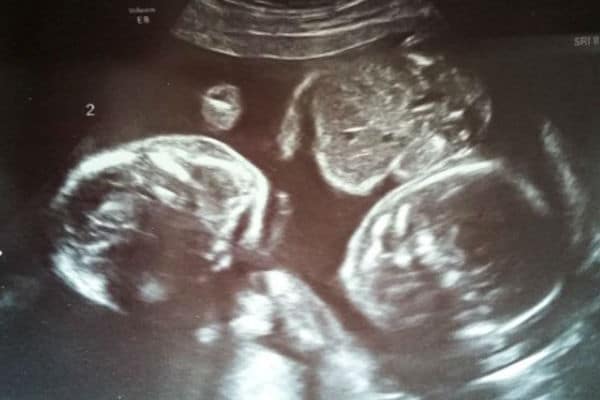

Havia muitos riscos como: os bebês se enrolarem nos cordões umbilicais e acabarem estrangulados. Entretanto, um milagre aconteceu: Os irmãos gêmeos ficaram quietinhos durante toda a gravidez. O ultrassom feito por Hayley mostrou uma situação muito curiosa, os bebês Rowan e Blake estavam bem aconchegados e de mãos dadas.